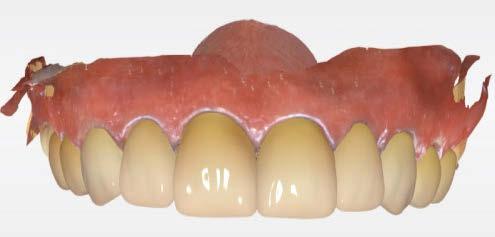

SW 5.2, Dentsply Sirona) (Figuras 22-27), la cual fue materializada en dos tipos de materiales a partir de bloques cerámicos IPS Empress CAD y cerámica vítrea de disilicato de litio IPS E.max CAD (Figuras 28-30)

Finalmente, las restauraciones se cementaron adhesivamente (Figuras 31-35). En las piezas 16 y 17 se realizaron restauraciones cementoatornilladas como última fase de tratamiento. Se recomendó al paciente una férula de protección superior la cual fue elaborada mediante un flujo de trabajo digital (Figura 36)

Figura 30. Restauracones impresas vista oclusal superior e inferior. Figura 29. Prueba de las restauraciones en modelo impreso en 3D. Figura 28. Bloques de IPS Empress CAD fresados. Vista frontal.